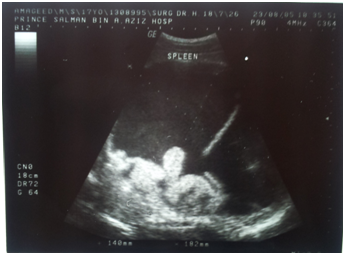

Figure 1 Ultrasonography of abdomen: revealed a cystic collection juxtaposed to the spleen.

2. Ultrasonography of abdomen: revealed a cystic collection juxtaposed to the spleen.